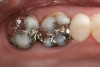

The milled and sintered zirconia substructure is fit to the SLA die model. The external surface of the zirconia substructure is air-abraded using Rocatec™ Soft (3M ESPE) to prepare it for fusion to the digital veneer. The digital veneer is carefully cut from the block holder and placed in distilled water for 1 minute to allow water to uniformly penetrate into the glass ceramic. The Lava DVS Fusion Porcelain is mixed in one of the 10 shades appropriate for the shade of the restoration and painted on the internal surface of the digital veneer. Additional fusion porcelain is placed on the external surface of the zirconia substructure, and the digital veneer is positioned over it. The excess fusion porcelain is expressed from between the two layers as the digital veneer is compressed to place over the substructure (Figure 15). The excess fusion porcelain is smoothed out at the margins, then fired in a porcelain oven. The final contours of the restoration are refined on the articulated SLA models. The final shade of the crown is influenced by the shade of the colored zirconia substructure, fusion porcelain, and the digital veneer. The fused crown can also be customized with surface stains and glazes (Figure 16). The case is returned to the dental office for delivery to the patient with a choice of adhesive or conventional cementation (Figure 17 and Figure 18).

Figure 16  Completely processed crowns.

Figure 16

Figure 17  Occlusal view of cemented crowns for teeth Nos. 2 and 3.

Figure 17

Figure 18  Facial view of the cemented crowns for teeth Nos. 2 and 3.

Figure 18